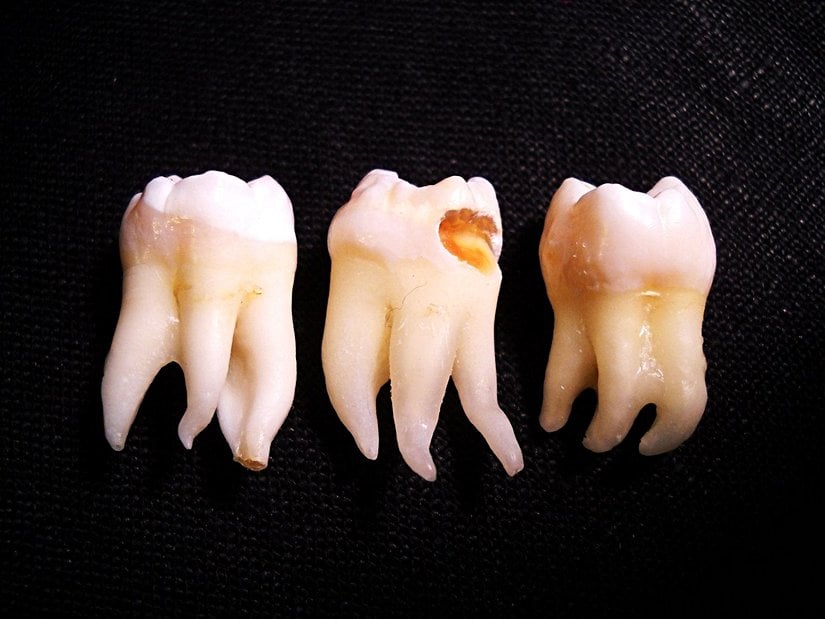

Yirmi yaş dişlerinin sıklıkla gömülü kalırlar, çıktıkları zaman doğru şekilde çıkmazlar ve diğer dişlere sürtünerek onların yapısını bozabilirler. Bu nedenle de ağrı ve enfeksiyona neden oldukları bilinmektedir. Bunun haricinde ise hiçbir işlevleri bulunmamaktadır. Dolayısıyla ağrıya neden oldukları zaman, diş hekimleri tarafından çekilerek hasta rahatlatılabilmektedir. 20 yaş dişleri çekilen kişilerin ağız fonksiyonlarında hiçbir azalma olmamaktadır. Aşağıda bu dişleri görmektesiniz: